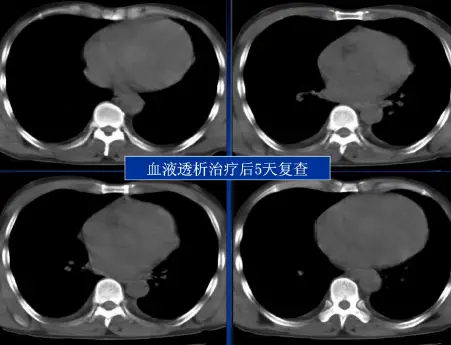

病例:男,33岁,急性肾衰肺水肿。CT表现:①肺间质性肺水肿:两肺血管束增多、增粗,边缘模糊;②肺泡性肺水肿:两肺透光度减低,并见广泛性分布结节样、斑片样密度增高影及毛玻璃样影,边缘模糊,以两肺内、中带分布较明显,形成典型“蝶翼征”;③胸腔积液。